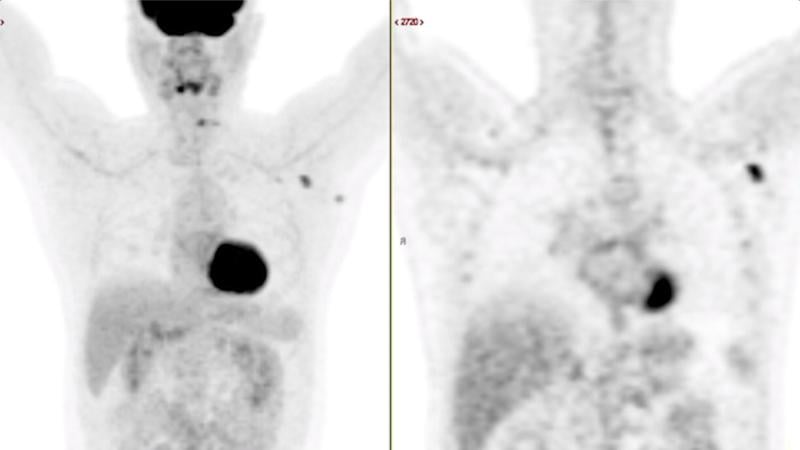

This photo gallery shows the variety of radiological presentations of COVID-19 (SARS-CoV-2) in medical imaging, including computed tomography (CT), radiograph X-rays, ultrasound, echocardiograms and magnetic resonance imaging (MRI). The radiology images show examples of typical COVID pneumonia in the lungs and the numerous complications the virus causes in the body in multiple organs, including the brain, kidneys, heart, abdomen and vascular system.